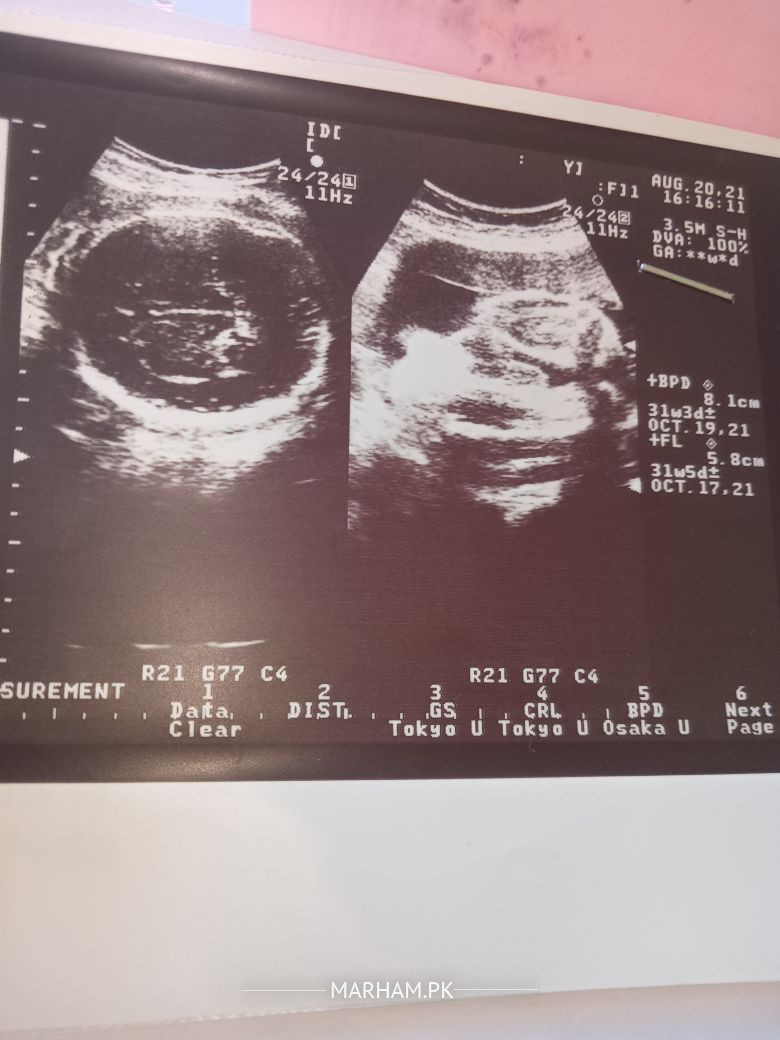

Aoa.. currently i am 38 weeks Pregnant, these are all my reports.. i want to know when should labour Pain start? which week should i deliver baby? i want normal delivery

what are the chances of normal delivery?? any complications written in reports?

AOA

WT is ur Bishop Score?means wt duz ur internal examination tells?how much is the baby weight?anu loop of cord around the neck?how about biophysical profile wth umblical artery doppler wth SD ratio?now tell wthout all these things who can predict?tawakul Allah...ethg ll b fine in sha Allah